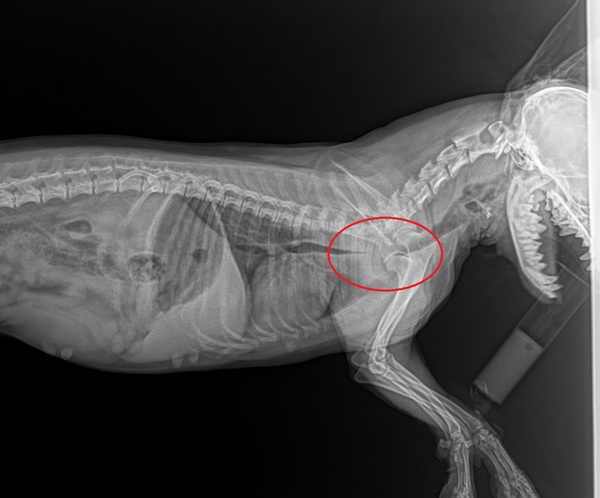

У меня йоркширский терьер по кличке «Оливия» живёт уже 7,5 лет. На днях я проснулся от того, что собака начала кашлять. У неё и раньше такое бывало когда она или волосинку проглотила или ещё что-то, и я не придал сначала этому значения. Но в течении 30 минут или часа она продолжала кашлять и выделять пену. Почувствовав неладное я собрался и поехал в ветеринарную клинику. Приехав новости были не утешительные, док сразу сказал, что собака задыхается. Он посмотрел глотку и там был отёк. Собаке укололи что-то внутривенно, чтоб она дышала и не задохнулась, далее сделали наркоз и осмотрели глотку, нет ли там косточки. Косточки не было, причина крылась в другом. Оперативно ей сделали рентген. И тут было ещё печальнее, у неё сужена трахея и из-за этого она практически не может дышать. Сказали что у неё полтора может два часа осталось. Можно якобы вставить какую-то трубку в трахею и расширить её принудительно, чтоб собака дышала нормально. Проблема заключается в том, что я нахожусь в г. Кривой Рог, а у нас такое в городе никто не делает хоть и город большой, делают в Днепре только в одной клинике. До Днепра 1,5 часа езды. У врача не было номера этой клиники, благо у меня друзья в Днепре и я сразу начал звонить узнавать где она находится и её номер телефона. Узнав номер клиники я позвонил туда и сразу возникла проблема, они эту процедуру делали, но нужно было отправить на почту снимки, чтоб они посмотрели есть ли эта "трубка" нужной нам длины в наличии. Я с горем пополам фотографирую рентген и не теряя времени с женой отправляюсь в Днепр, соответственно жду звонка с клиники с хорошими новостями. Проехав треть пути мне поступил звонок от администратора клиники, который поверг меня в шок. Девушка сказала, что нужной нам длины есть трубка, и озвучила стоимость и сказала, вы подумайте и перезвоните. Стоимость была мягко говоря не маленькая, тем более что у меня с собой была только треть денег, так как я не ожидал, что это может столько стоить. Стоимость этой процедуры около 600$. Немного отойдя от шока, я начал звонить друзьям в Днепр и просить денег в займы, так как возвращаться в город и терять 1,5 часа, чтоб искать деньги у меня не было времени, точнее у нашей девочки не было времени. Я договорился за деньги с другом и мы продолжили путь в Клинику. Дальше продолжу без воды только суть. Приехали в клинику, нас приняли и сразу же отправили жену с собачкой дышать кислородом, а я в это время ждал в машине. Кислородом дышали около часа, потом повторно сделали рентген. Ещё раз убедившись на своём оборудовании в проблеме, проверили размер необходимой трубки и приступили к делу. Оливии сделали Наркоз и ассистентка хирурга понесла её в операционную. Нам сказали операция продлится около часа. Мы пошли с женой покушали пришли где-то через пол часа, но нас уже ждали, хотя нашу Оливку не выносили ещё. Прошло ещё 40 минут и нам вынесли нашу девочку, она отошла от наркоза сразу узнала нас, и хоть была вялая начала облизывать руки. После вышел хирург, на вид около 40 лет, но отзывы хорошие о нём. Говорят, что он берётся за операции, которые в других клиниках не видят смысла даже делать и результаты положительные. В общем операция прошла успешно, ну как операция, никакого хирургического вмешательства не было, ей через глотку это всё делали, видео прилагаю. Врач сказал, что эта трубка должна в течении 2-х недель прижиться и присосаться к слизистой, а пока она будет покашливать из-за дискомфорта. Но гарантии, что всё будет хорошо не дают! Прописали кое какое лекарство для восстановления, антибиотик и ещё что-то. На данный момент прошло двое суток и улучшения есть. В первые сутки после этого Оливка еле ходила, чувствовалась вялость и бессилие. На данный момент она кушает и передвигается бодрее, лает и запрыгивает на кровать.